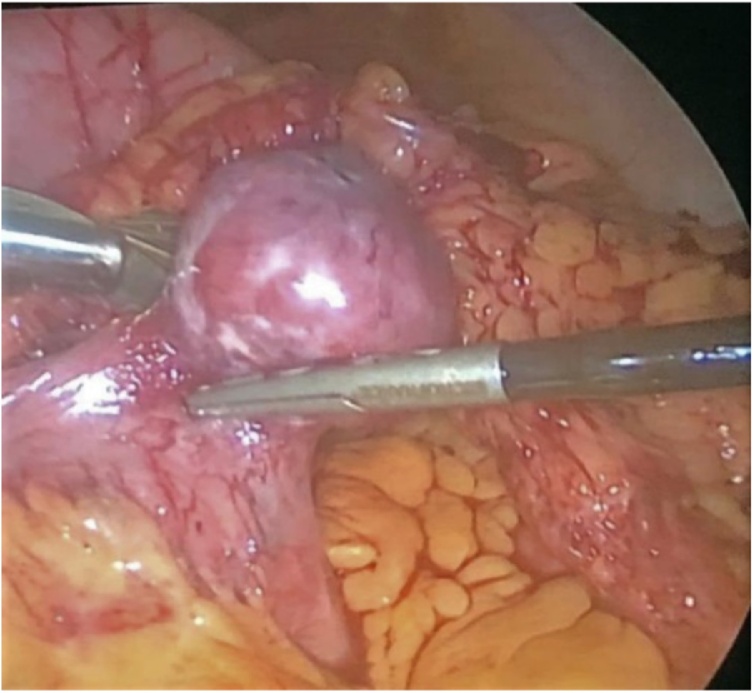

The patient was transferred to our surgical department where we performed an exploratory laparoscopy. Surprisingly, we found a mass at the level of the first jejunal loop about five centimetres from the Treitz ligament (Fig. 4). We performed a laparoscopic wedge resection using a linear stapler (Fig. 5a, b). Moreover, there were multiple nodules in the whole small bowel wall (Fig. 6). The final surgical result highlighted the cosmesis and typical café-au-lait spots as well as multiple skin nodules (Fig. 7). The surgical team was skilled in laparoscopic surgery. In the post-operative period, an episode of anaemia was treated with two hematic transfusions (Grade II according to Clavien-Dindo classification of surgical complications). The abdominal drain, normal during the initial postoperative period, showed a clear liquid and laboratory tests confirmed the presence of lipase and amylase which resolved followed the administration of octreotide. On the 16th postoperative day (POD) she had a significant episode of melena and dark blood with an haemoglobin 7.4 g/dl receiving one unit of packed red cells. Postoperative evolution was favourable, and she was discharged home in good clinical conditions.

Fig. 4.

Intraoperative view - A mass at the level of the first jejunal loop about five centimetres from Treitz ligament.